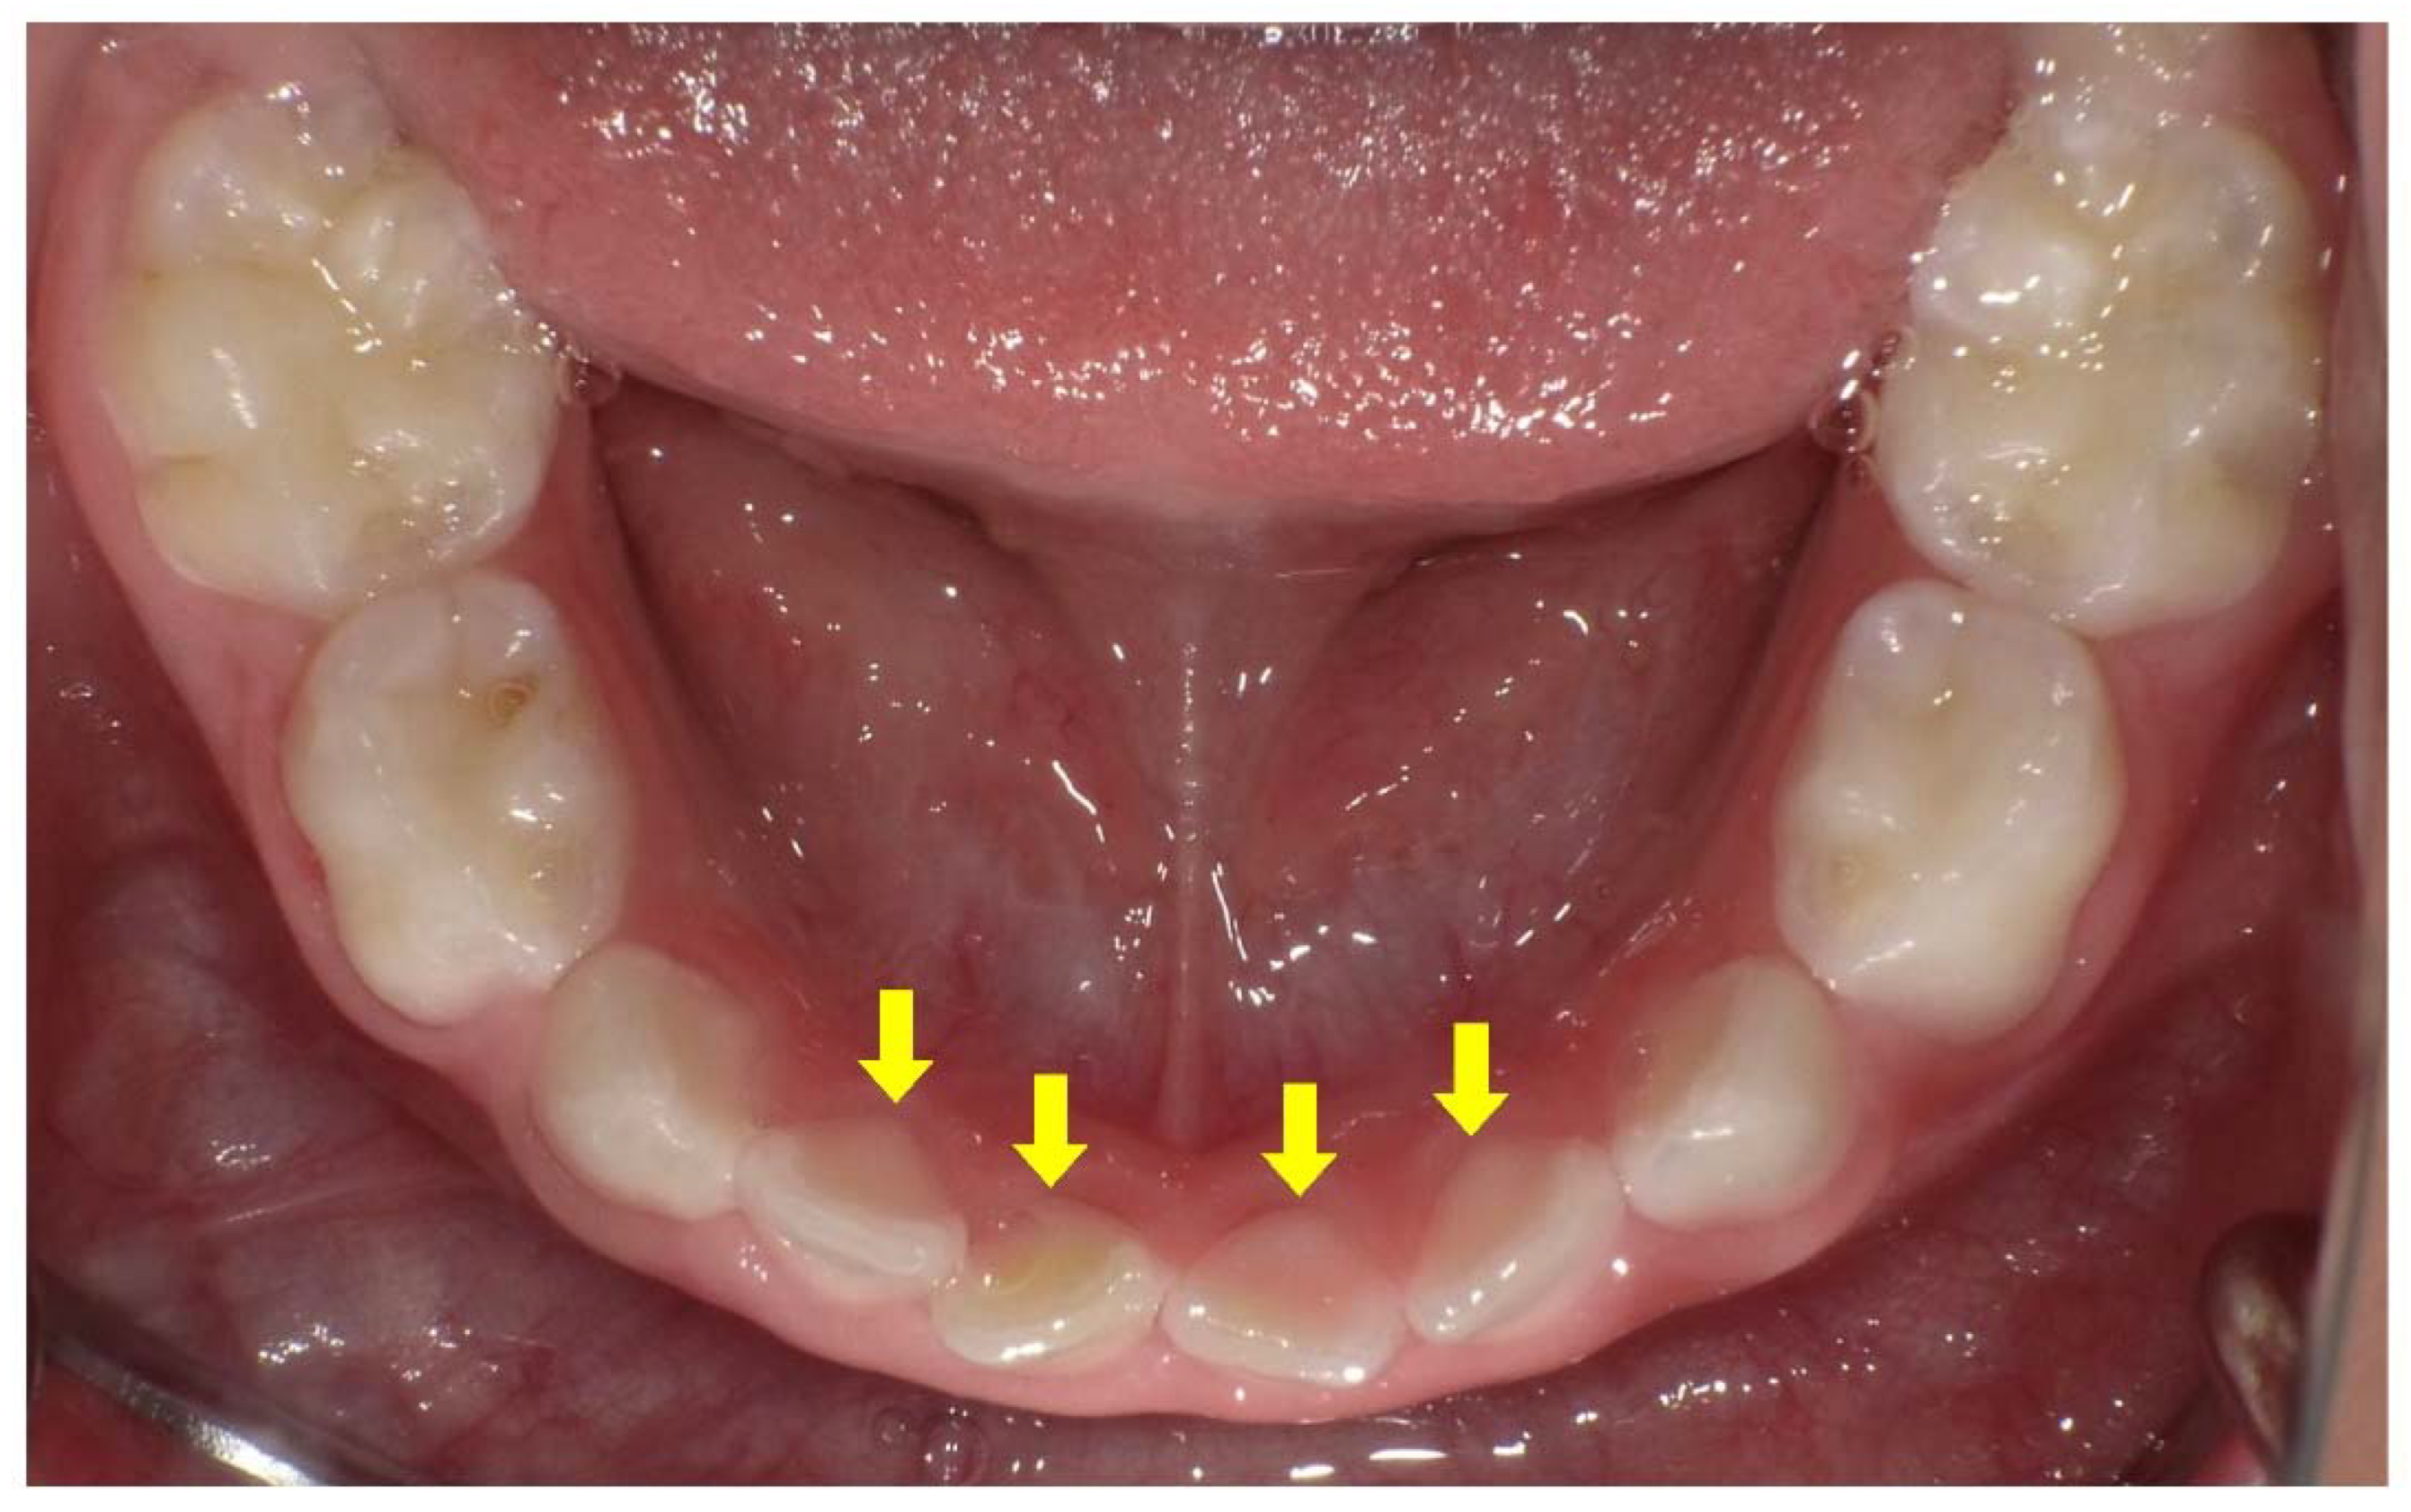

Figure 5.

Intraoral photograph of the mandibular arch of a male X-linked hypophosphatemia (XLH) patient aged 3 years 3 months. The pink color of the pulp can be seen through the enamel on the lingual side of the primary mandibular incisors (arrows).